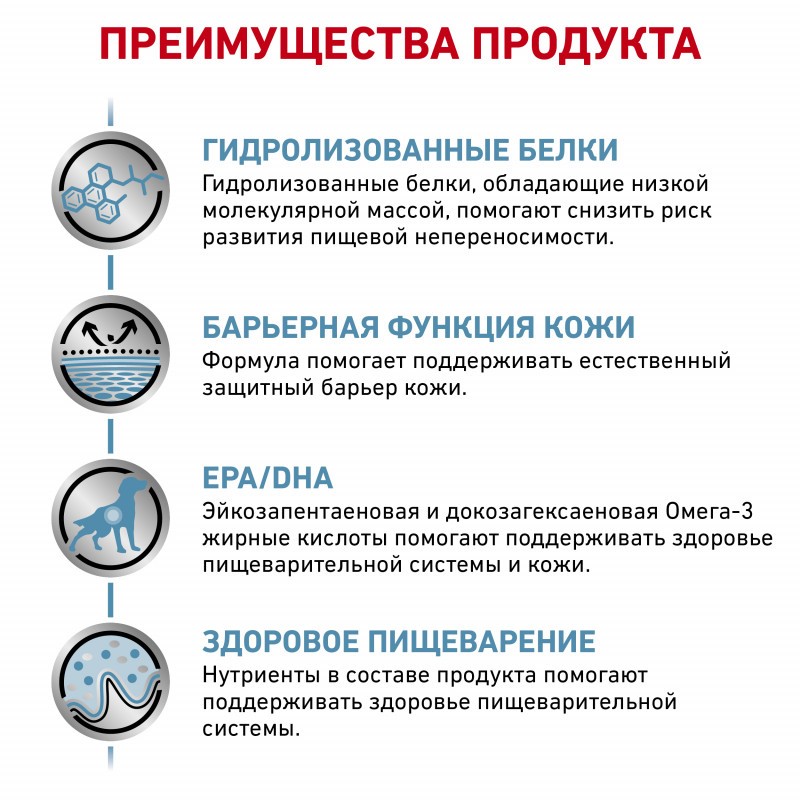

ПРЕИМУЩЕСТВА КОРМА

Гидролизованные белки, которые обладают низкой молекулярной массой, максимально снижают риск развития аллергических реакций.

Формула помогает поддерживать естественный защитный барьер кожи.

Для поддерживать здоровья пищеварительной системы и кожи, в составе эйкозапентаеновая и докозагексаеновая Омега-3 жирные кислоты.

Наличие в составе нутриентов помогают поддерживать здоровье пищеварительной системы.